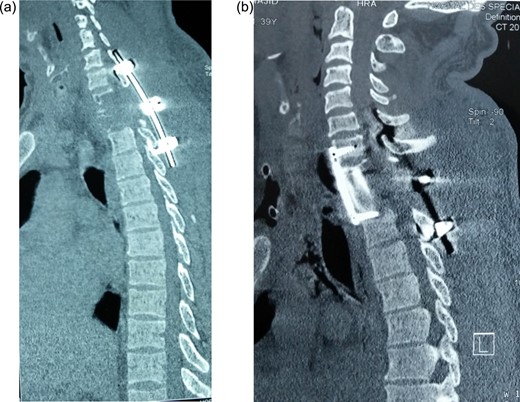

Postoperative sagittal CT showing (a) hook and rod stabilization posteriorly, and (b) bone graft and plate fixation anteriorly after corporectomy of D1 and D2.